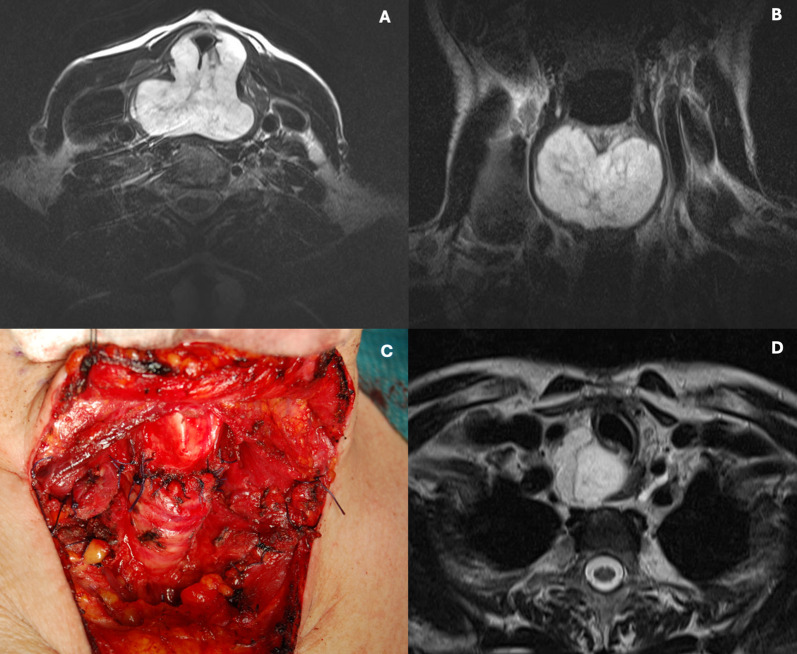

Abstract Image